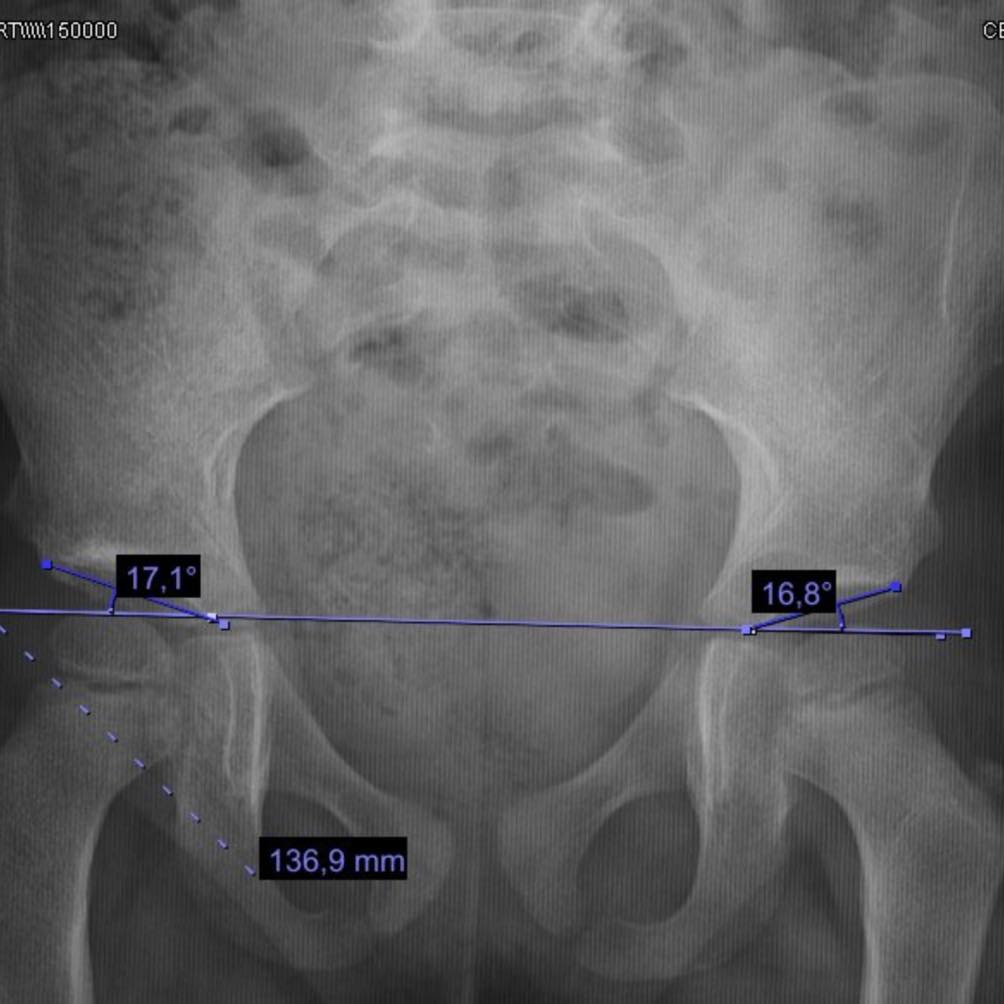

Ayer tuvimos la enorme alegría de dar de alta a Valentina, una pequeña de 3 años. Llegó a consulta y le detectamos una displasia de cadera que, lamentablemente, no se identificó a tiempo por la falta del tamiz de cadera. Le realizamos la cirugía para corregir la displasia y hoy sus caderas están dentro de parámetros normales. Con este tratamiento, logramos prevenir un desgaste prematuro y reducir la necesidad de una prótesis en el futuro. ¡Gracias, Valentina, por los panes de muerto que nos trajiste!